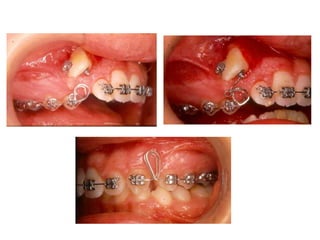

TRANSPOSIÇÃO TOTAL - CANINO COM INCISIVO LATERAL MANOBRAS PARA CORREÇÃO DA ROTA DE ERUPÇÃO